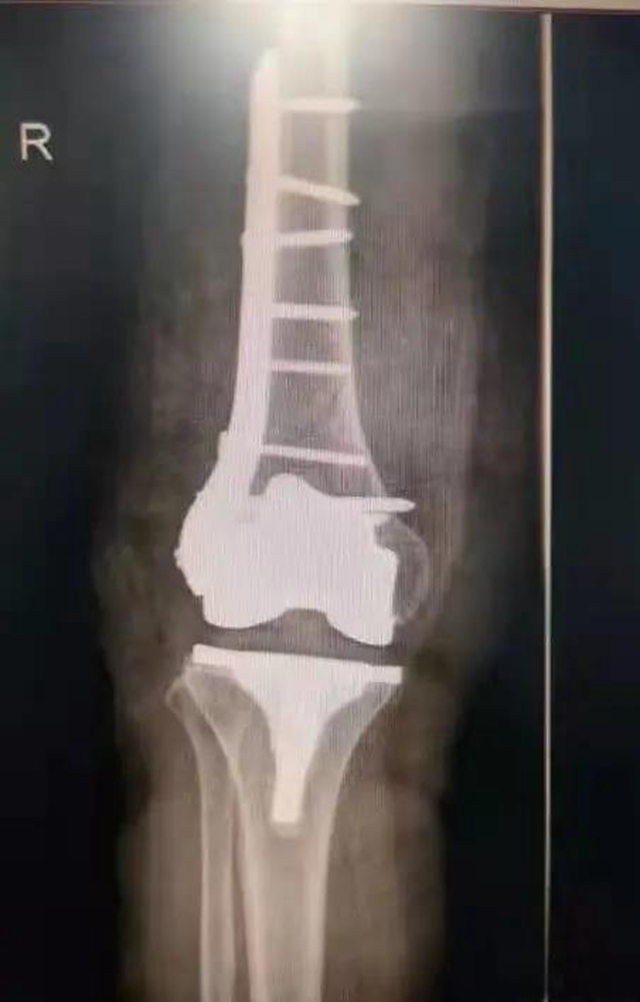

术后

12月7日,在医护团队的默契合作下,历时1个多小时,吴阿姨的手术顺利完成。经过两周的后续治疗,吴阿姨已经可以站起来,借助拐杖行走。“医生们这次又让我站起来了。”吴阿姨开心地说。

“关节假体需要进行‘翻修’固定,要保证骨折部位修复后假体的稳定性,还要考虑患者年龄大,曾接受过多次手术,患有多种基础疾病,手术技术难度高,对医生和患者都是一次挑战。”作为手术团队成员和吴阿姨主管医生的王旌晶觉得一定要对得起患者及家属这份沉甸甸的信任。